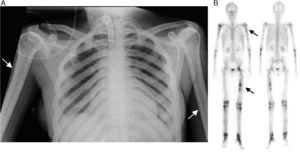

The patient was a 37-year-old woman, with a personal history of muscle weakness, pain in lower limbs and a waddling gait with claudication since she had been 18 months old. In a chest radiography carried out for dyspnea, it was incidentally found that she had generalized demineralization, with thickening of the diaphyseal cortical bone of the long bones (Fig. 1A, arrows). Given these findings, she underwent whole body bone scintigraphy, to determine the extension of the involvement (Fig. 1B, arrows), which revealed large areas with an increase in osteoblastic activity in the diaphysis of the long bones of her upper and lower limbs, as well as involvement of left hip, knees and tarsus, with different degrees of activity. Molecular genetic testing resulted in the definitive diagnosis of Camurati-Engelmann disease. The genetic diagnosis was subsequently reached in 4 first-degree members of her family with a history of pain in lower limbs and proximal muscle weakness.

(A) Anteroposterior chest radiography showing the irregular thickening of the diaphyseal cortical bone of the long bones, especially in both humeri. This bilateral and symmetrical cortical thickening is also evident in the clavicles, greater in the medial area. (B) Whole body bone scintigraphy in anterior and posterior images, showing multiple abnormal uptakes of 99mTc-diphosphonates with different uptake intensity, in relation to the osteoblastic activity, which is more evident in diaphyseal regions of the long bones and left hip.